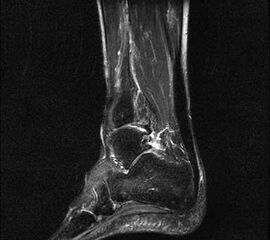

Hier befindet sich ca. 3-5 cm proximal des Tuber calcanei ein als „kritische Zone“ benannter Bezirk, der durch eine ungünstige arterielle Blutzufuhr gekennzeichnet ist (letzte Wiese). Hier finden sich häufig spindelförmige Schwellungen, die bei MRT-Diagnostik nicht selten partielle Nekrosen und Partialrupturen der Achillessehne aufweisen (Abb. 14).

Unabhängig davon können insbesondere chronische Insertionstendinosen der Achillessehne von Partialrupturen (Abb. 15) und erosiven Läsionen des dorsalen Fersenbeines begleitet sein.

Bildgebung

Die sonographische Diagnostik eignet sich primär zur Erkennung schmerzhafter Prozesse im Verlauf der Achillessehne und kann bei Bedarf durch Röntgen bzw. MRT ergänzt werden. Besonders bei längeren Verläufen und kräftigen spindelförmigen Schwellungen (>9mm, Normwert <5mm) im Bereich der kritischen Zone sollte ein MRT zum Ausschluss von Nekrosezonen und Partialrupturen vor Therapiebeginn veranlasst werden. Die sonographisch leicht zu erfassende Veränderung der Sehnendicke im mittleren Sehnenanteil ist ein guter Indikator für die Schwere der Erkrankung und die Beurteilung des Behandlungsverlaufes. Die sichtbaren Veränderungen am distalen knöchernen Ansatz der Sehne sind diskreter.

Insbesondere bei größeren Partialrupturen (Abb. 14) sollten operative Verfahren erörtert werden. Kleinere Partialrupturen sind der ESWT gut zugänglich, wie die beiden nachfolgenden Beispiele zeigen: